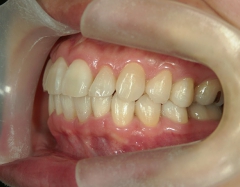

矯正歯科 治療前矯正歯科 治療前

プチワイヤー矯正 症例(23

41歳女性 浜松市浜北区在住

治療期間 1年3カ月

主訴:下の前歯の歯並びが乱れていて、舌に当たって痛い。